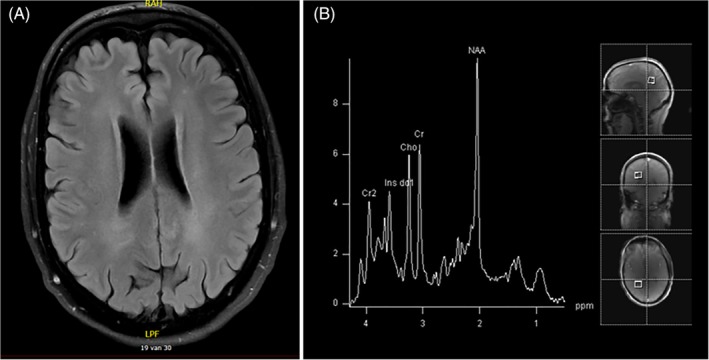

Cerebral MRI showed diffuse, subtle signal changes of the periventricular white matter without other abnormalities. MRS revealed normal spectra of the parieto‐occipital white and occipital gray matter, and (thus) did not show the typical “lipid peak” at 1.3 ppm (Figure 3).11 FALDH activity in lymphocytes was below detection limit of the enzyme assay. Sanger sequencing showed compound heterozygosity for two pathogenic variants in the ALDH3A2 gene, namely, c.682C>T (p.[Arg228Cys]) and c.943C>T (p.[Pro315Ser]).

Figure 3.

Cerebral magnetic resonance imaging and spectroscopy of patient 1. A; T2‐weightened MRI scan with subtle abnormalities in the periventricular white matter. B, MRS from the white matter, without the characteristic lipid peaks. MRI, magnetic resonance imaging; MRS, magnetic resonance spectroscopy

Applying MRS, lipid accumulation can be demonstrated in cerebral white matter of patients with classic SLS. Remarkably, the spectra of patient 1 did not show the typical resonances reflecting lipid accumulation. The other mildly affected Dutch patient known in our center, the sister of patient 2, did not demonstrate the typical lipid peak on MRS in previous studies.7, 10 The absence of lipid accumulation, or at least much lower brain tissue concentrations of abnormal lipids (below the detection limit of MRS), might be one of the explanations for the mild neurological phenotype.